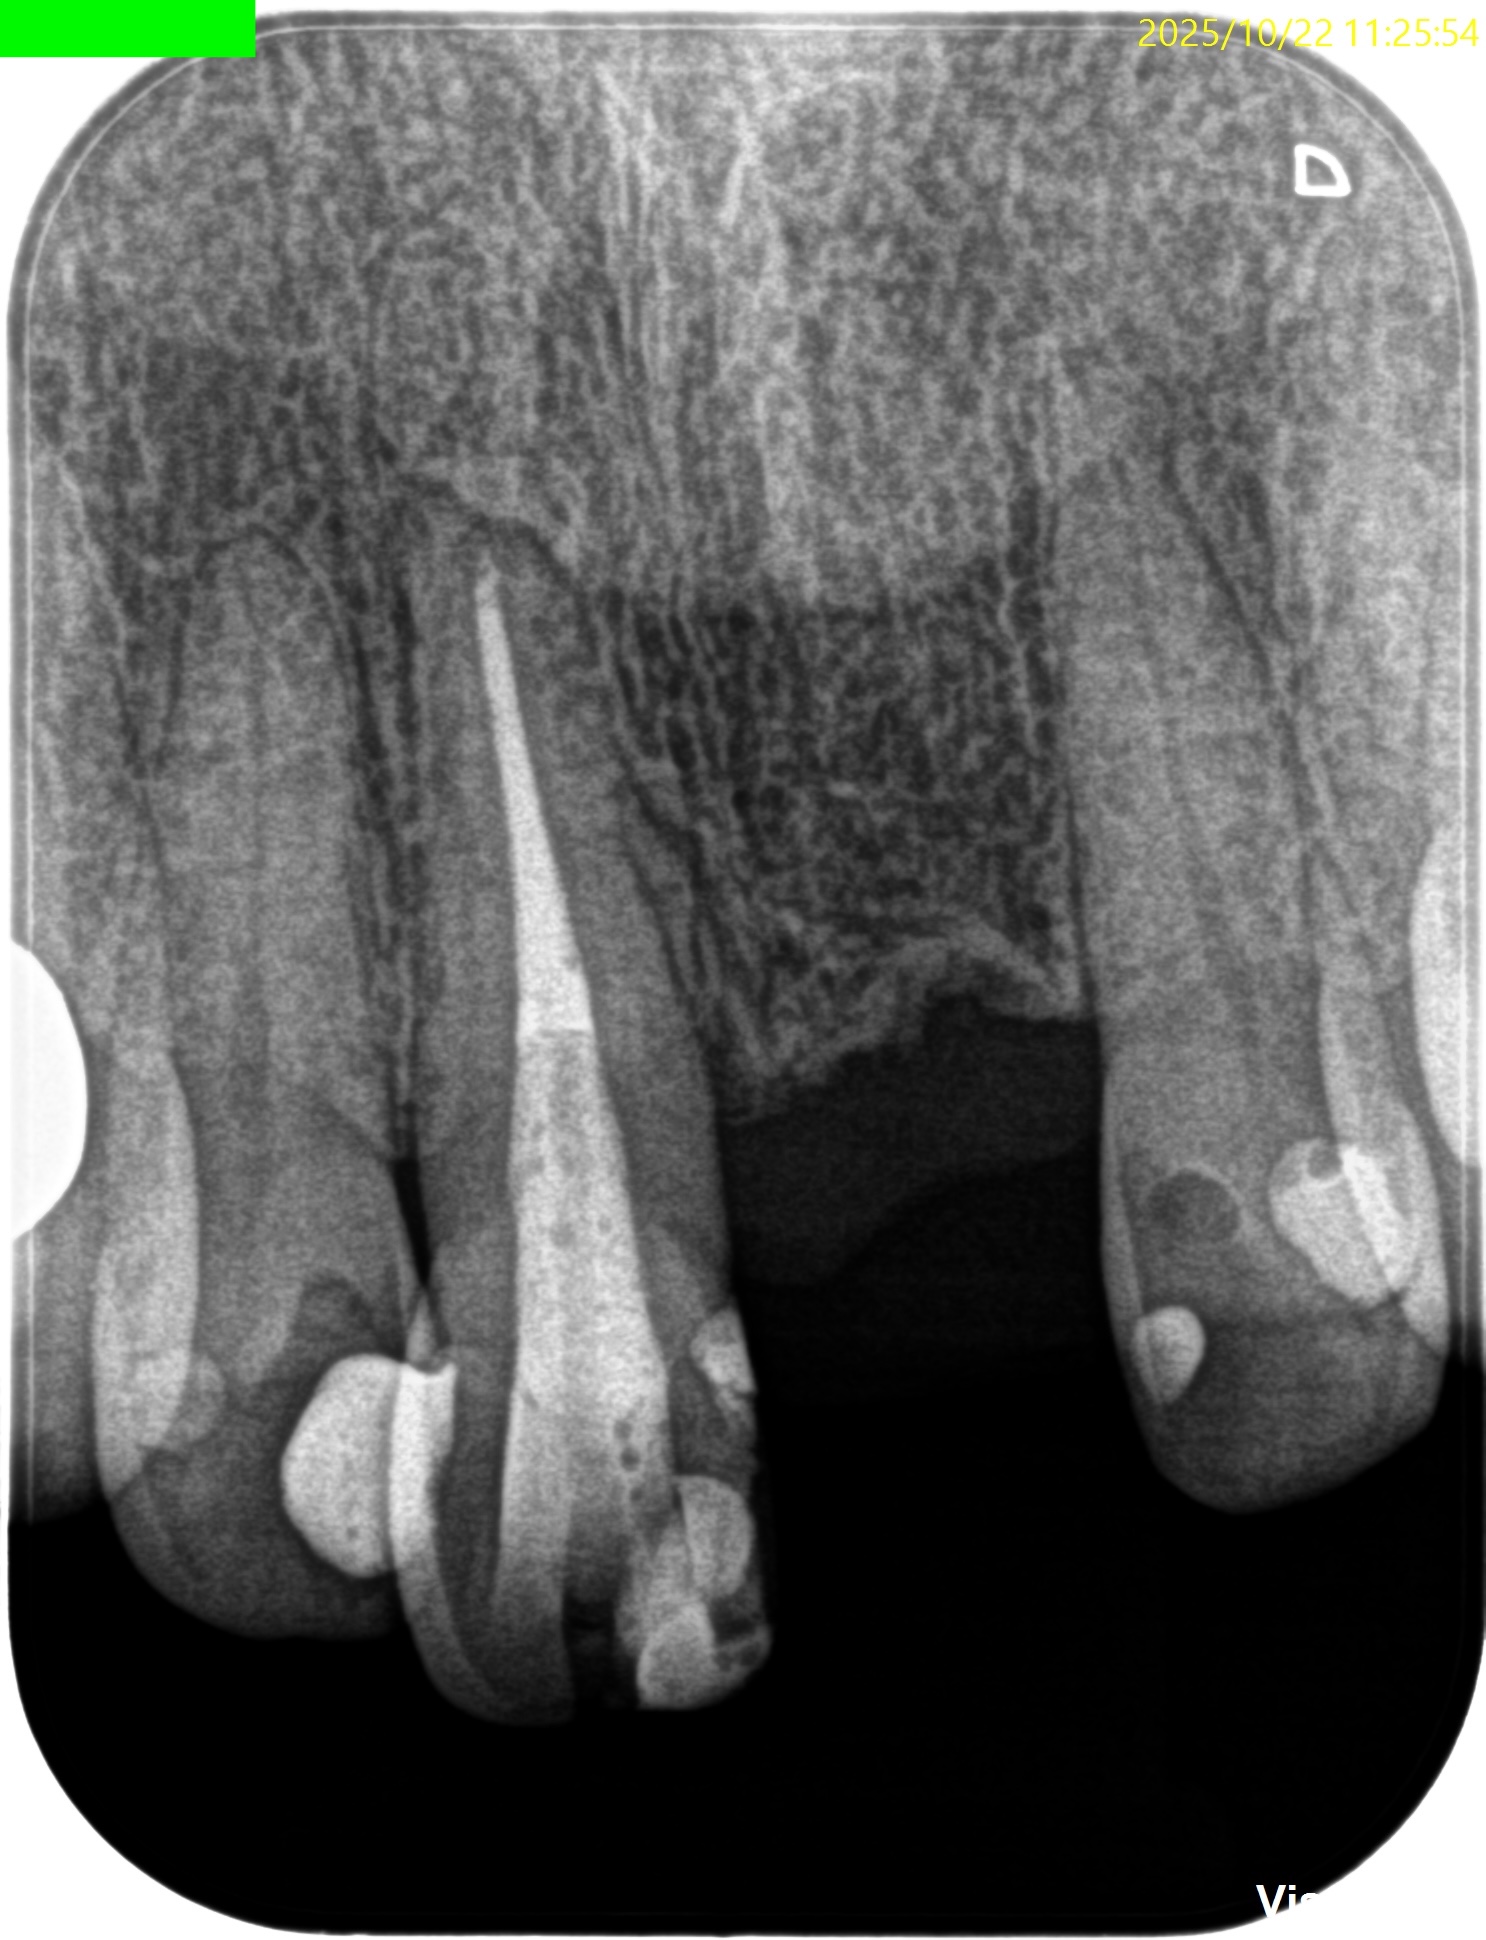

PA(2025.10.22)

この部分を攻略できれば勝機がある可能性が90%あるだろう。

攻略できなければ60%だ。

歯内療法学的診断(2025.10.22)

Pulp Dx: Previously treated

Periapical Dx: Symptomatic apical periodontitis

Recommended Tx: Re-RCT+Core build up with Fiber Post